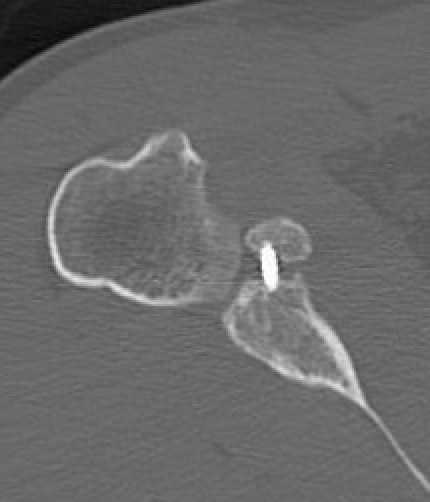

Bone block positioning

Concepts

- coracoid must not overhang medial to avoid osteoarthritis

- coracoid < 5 mm medial to glenoid rim

- coracoid lower half of glenoid 2 - 5 o'clock

- fixation screws purchases posterior glenoid cortex

- screws do not penetrate articular surface

Traditional Latarjet v Congruent arc

- align concave inferior surface coracoid with medial concave glenoid

- graft is thinner in this position, making screw fixation more difficult

Graft malposition

Screws and graft too medial

Bone graft too medial

Coracoid graft too superior on glenoid